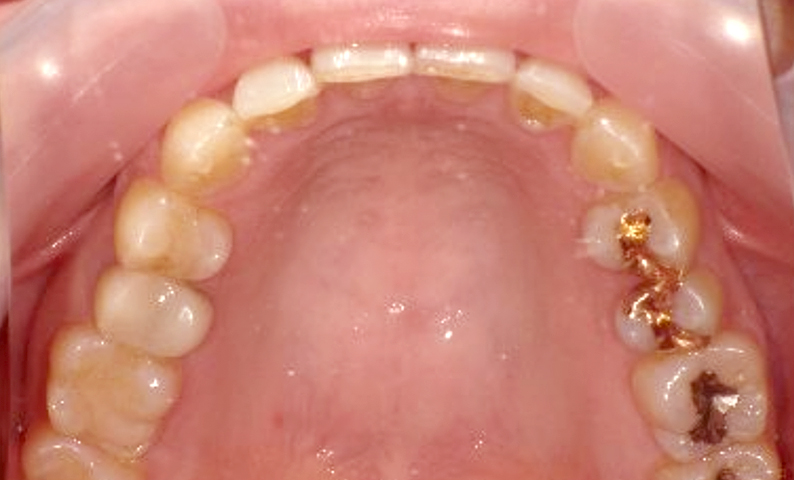

症例_002 下顎だけの部分矯正

治療期間:6ヶ月金額:21万円+税女性前歯のデコボコ下の前歯だけ

| Before | After |